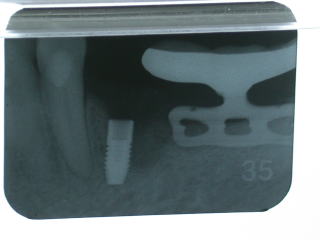

約半年待って左下4にインプラントを植立しました。

その後半年、粘膜下でインプラントが骨と良く結合するの半年間待ちます。